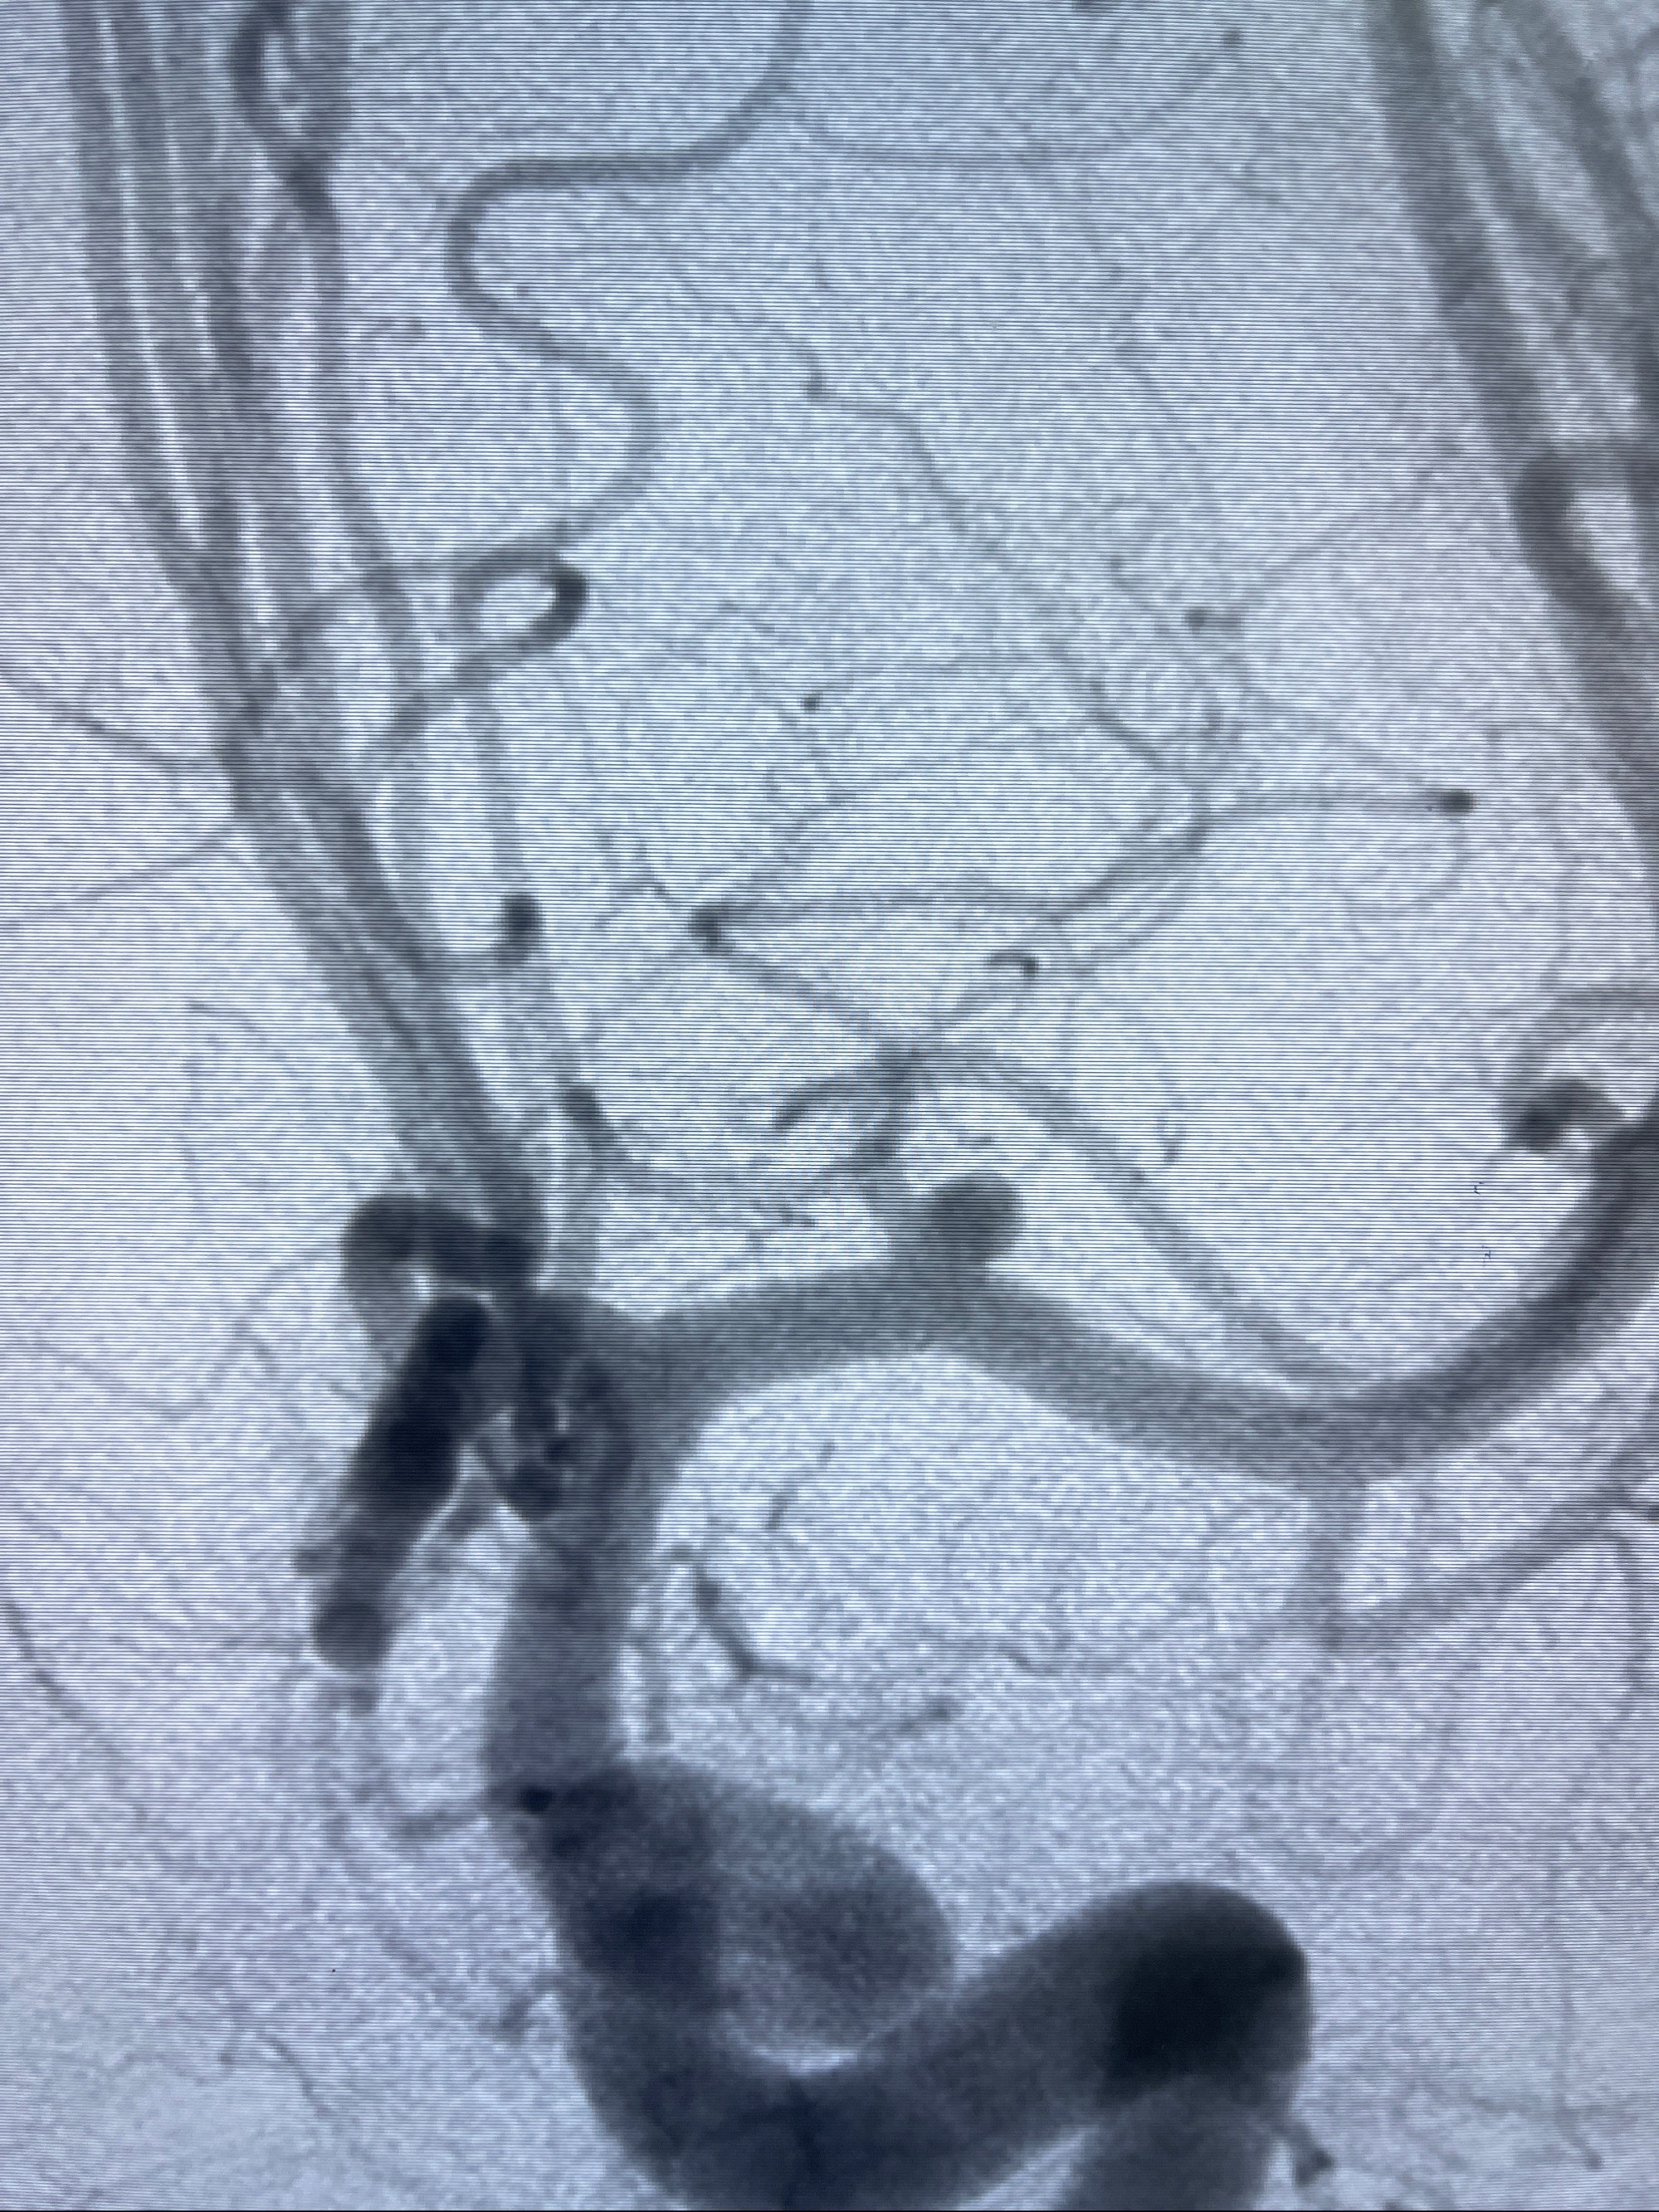

2023-08-14DSA:

左侧大脑中动脉动脉瘤,约2.6-2.8-3.4-2mm大小(瘤颈部、瘤体部、瘤高)

2.外科手术夹闭or介入支架辅助栓塞